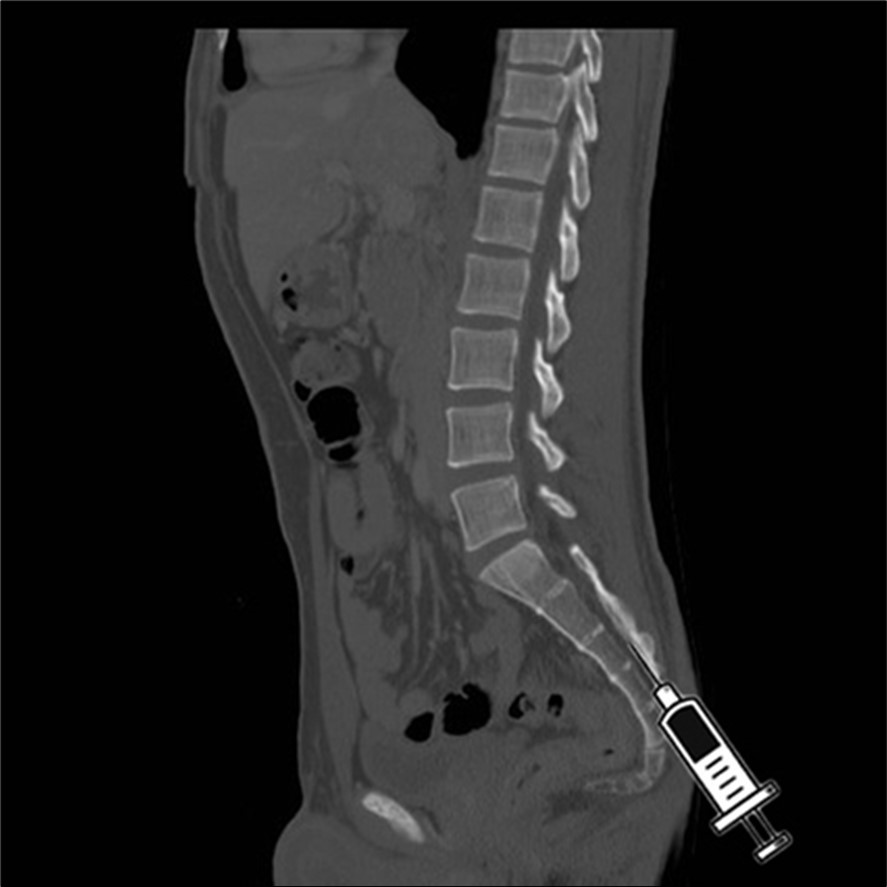

Sacral injections, also known as caudal epidural injections (Figure 2- Figure 3), can be an effective treatment option for some individuals with lower back pain. These injections involve injecting numbing medicine and a steroid into the epidural space near the tailbone to alleviate nerve pain and inflammation. While the effectiveness of sacral injections varies among patients, they are generally considered safe with minimal risks of complications.

Figure 3.sagittal C.T. scan view of the injection in the hiatus.